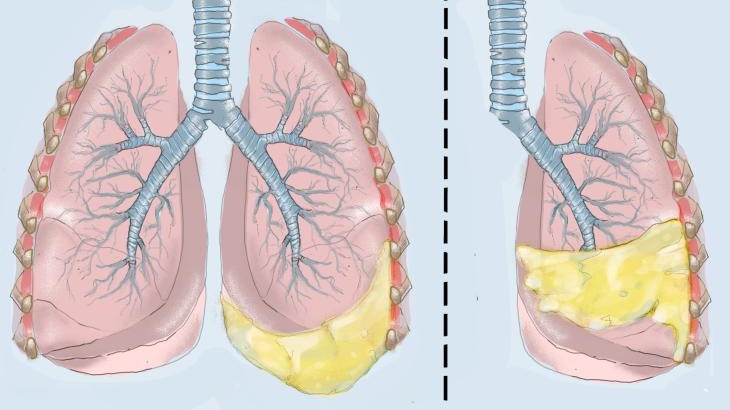

Hội chứng Meigs là bộ ba dấu hiệu gồm khối u buồng trứng lành tính, cổ trướng và tràn dịch màng phổi - cả ba vấn đề này có thể giải quyết sau khi cắt bỏ khối u. Fibromas buồng trứng chiếm đa số các khối u lành tính trong hội chứng Meigs. Hội chứng Meigs là một chẩn đoán phụ chỉ được nghĩ đến sau khi loại trừ ung thư biểu mô buồng trứng.

Dịch cổ trướng và dịch màng phổi trong hội chứng Demons Meigs có thể là dịch thấm hoặc dịch tiết. Sinh lý bệnh của cổ trướng và tràn dịch màng phổi trong hội chứng Demons Meigs chưa được xác định rõ ràng. Meigs đưa ra giả thuyết rằng cổ trướng là do áp lực của khối u lên hệ bạch huyết ở bụng và dịch cổ trướng sau đó sẽ thấm vào khoang màng phổi. Phù nề mô đệm có thể dẫn đến dịch tiết do thay đổi hệ thống dẫn lưu tĩnh mạch và bạch huyết. Sự mất cân bằng giữa nguồn cung cấp máu cho một khối u và hệ thống thoát nước tĩnh mạch và bạch huyết có thể là nguyên nhân gây ra phù nề và tăng dịch tiết mô đệm.

Các triệu chứng liên quan đến tràn dịch màng phổi bao gồm khó thở, ho khan và viêm màng phổi. Tràn dịch màng phổi thường ở bên phải, mặc dù có thể xảy ra tràn dịch màng phổi bên trái và hai bên. Lượng dịch của tràn dịch màng phổi không phụ thuộc vào lượng dịch cổ trướng.